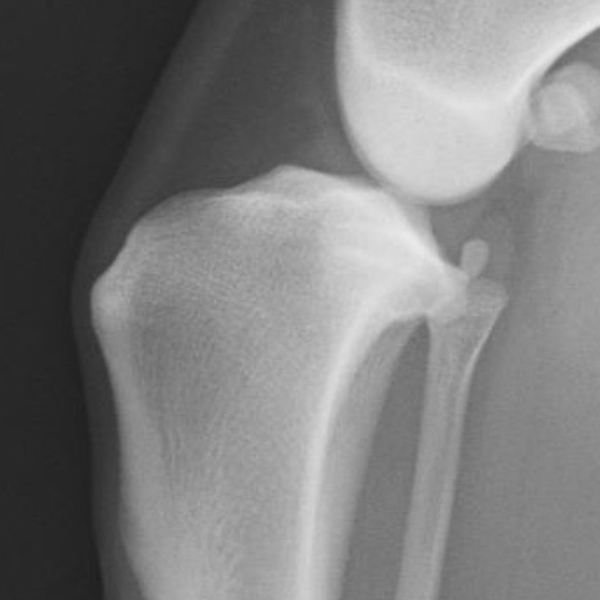

X線検査

レントゲン検査では、大腿骨と脛骨の位置関係や関節包の腫れ、腫瘍性疾患の存在を示唆する骨吸収像の有無などを確認します。写真の○と△は大腿骨と脛骨の位置関係を示しています。正常な位置関係では△の青丸と○の青丸が重なるように位置していますが、靭帯断裂症例では、両者の青丸がズレていることが確認できます。